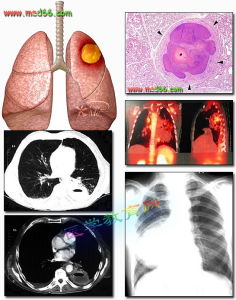

透視可見囊腫隨呼吸運動改變其大小。此症在肺內表現為圓形或類圓形陰影,邊緣清晰銳利,在與支氣管相通之前,表現為較高密度且均勻的影像,如與支氣管相通且氣體進入囊腫後,出現氣液平及單腔或多腔表現。如囊腫感染,其邊緣不清,周圍組織肺炎症表現。

右肺上葉支氣管囊腫CT1.單個液氣囊腫:最為常見,囊腫大小不一,可見圓形薄壁囊腫,內有液面。此種囊腫的特點是囊壁菲薄,鄰近肺組織無炎性浸潤病變,纖維性變不多,需與肺膿腫,肺結核空洞和肺包蟲囊腫鑑別。在X線上表現肺膿腫壁較厚,周圍炎症表現明顯,肺結核空洞則有較長病史,周圍有結核衛星灶。肺包蟲囊腫有流行病學的地區特點、生活史和職業史、血像、皮內試驗等有助於鑑別。

2.單個氣囊腫:胸片上示病側肺部含氣囊腫,巨大的氣囊腫可占據一側胸腔,壓迫肺,氣管,縱隔,心臟,需與氣胸鑑別。氣胸的特點是肺萎縮推向肺門,而氣囊腫的空氣位於肺內,往往仔細觀察在肺尖和肋隔角處可見到肺組織。

3.多個氣囊腫:臨床也較多見,胸片上呈現多個大小不一、邊緣不齊的氣囊腫,需與多個肺大皰鑑別。尤其在小兒,肺大皰常伴有肺炎,在X線上以透亮圓形薄壁大皰及其大小、數目、形態的易變性為特徵。每在短期隨訪中就見較多變化,有時可迅速增大,或破裂後形成氣胸。肺部炎症一旦消退,大皰有時可自行縮小或消失。

4.多發性液、氣囊腫:胸片上可見多個大小不一的液、氣腔。尤其病變位於左側者,需與先天性膈疝鑑別,後者也可呈現為多個液平,必要時口服碘油或稀鋇檢查,若在胸腔內見到造影劑進入胃腸道,則為隔疝。

典型的放射學表現為邊緣清楚、單發、圓形或橢圓形陰影,位於下葉的中三分之一,陰影的大小和形狀很少隨時間而改變,雖然也可見到數年後稍有增大者,75%於支氣管相通,並引起感染,相通後含氣,這類感染病人可因周圍炎性組織而使陰影邊緣變得模糊,而囊腫的陰影特性只有在感染消退後才能顯出。